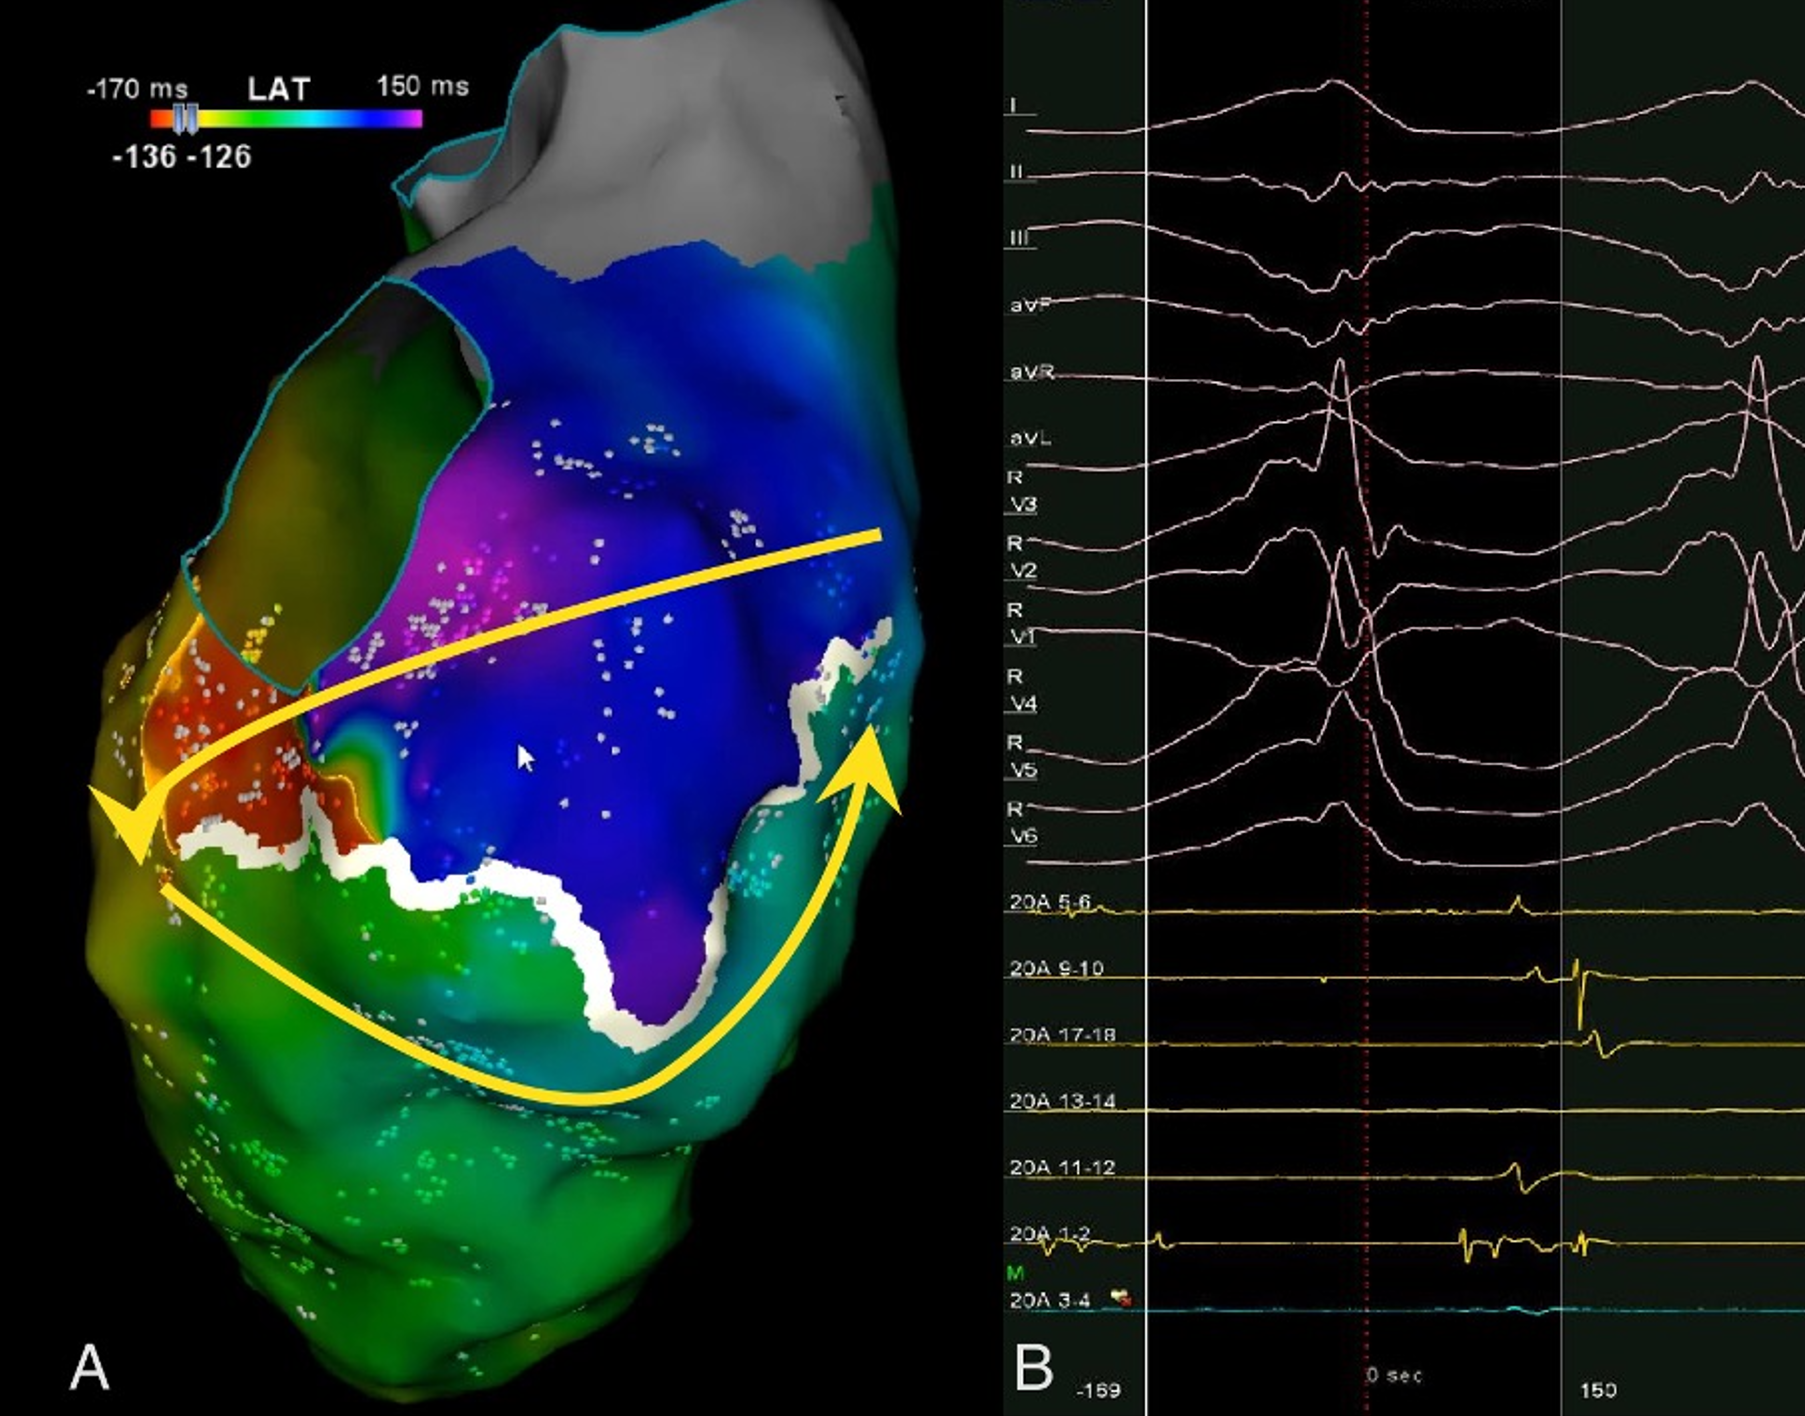

A 13-year-old male patient was admitted with complaints of chest pain and shortness of breath with exertion for 2 months. He was referred to our institution with a prediagnosis of ARVC and heart failure. Physical examination findings were as follows: Mild tachycardia (120-130 bpm), tachypnea (38/min), a 2-3/6 pansystolic murmur best heard at the left lower sternal border, jugular venous distension, a liver palpable 3 cm below the costal margin and mild ascites. Electrocardiogram showed; sinus tachycardia (110 bpm), a widened QRS (120 msec) and the corrected QT interval (QTc) of 480 msec (because of widened QRS) (Fig. 1). Echocardiography revealed significantly reduced biventricular function (left ventricle M-mode ejection fraction: 15%), enlarged right heart chambers with a RV diameter of 53.8 mm (z score: + 4.08) in apical 4 chamber view and severe tricuspid regurgitation (Fig. 2). Cardiac MRI showed marked dilation of the right ventricle (RV) with an indexed volume of 149 mL/m2 and hypokinesia in the free and inferior walls, as well as segmental wall thinning and focal late gadolinium enhancement (Fig. 3). The ejection fraction was 10% and 15% for the right and left ventricles, respectively. Heart failure treatment was administered immediately and a 24-hour-rhythm Holter was planned. On the second day of hospitalization, the patient had a sudden cardiac arrest and during cardiopulmonary resuscitation, it was recognized that the patient had VT exhibiting LBBB morphology with an intermittent transition to ventricular fibrillation (VF). Multiple antiarrhythmics including lidocaine, amiodarone, and magnesium were administered and the arrhythmia was converted to sinus rhythm after 5 cardioversions and 2 defibrillations. The patient was transferred to the pediatric intensive care unit (PICU). During follow-up in the PICU, the patient had episodes of LBBB morphology VT with intermittent transition to VF despite amiodarone and lidocaine infusion and was re-arrested. During cardiopulmonary resuscitation (CPR), venoarterial extracorporeal membrane oxygenation (ECMO) was initiated in 35 minutes. As drug-resistant VT storm continued during ECMO support, a single staged endocardial and epicardial approach for ablation was planned along with the assistance of cardiothoracic surgery. Even though the epicardial scar was much larger than the endocardial scar, a clinical VT isthmus was present at the endocardial site where ablation terminated the VT quickly (Fig. 4). An implantable cardiac defibrillator was implanted for secondary prevention, amiodarone was administered, and the patient was decannulated on the 4th day. The patient was discharged without any sequelae meanwhile autosomal dominant mutation that is linked to ARVC was detected in DSC2 gene at 18q12.1. Three months later the patient was rehospitalized for decompensated heart failure (NYHA class III-IV). Following this, his clinical status deteriorated due to multidrug refractory and inotrope-dependent heart failure. His kidney functions worsened, he became symptomatic even at rest, and developed massive hepatomegaly and ascites which required multiple paracentesis but never experienced sustained and hemodynamically significant arrhythmia. He could not be discharged and was on inotropes for 12 months till he underwent a successful heart transplantation. Pathological analysis of the explanted heart revealed: diffuse degenerative changes characterized by nuclear hyperchromasia, centralization and pleomorphism, areas of mucinous degeneration and oedema under the endocardium, mucinous degeneration in the valves, fibrosis between muscle fibers, congestion and fibrin accumulation sites in the pericardium and also a quite thin right ventricle wall. The patient has been followed up for 9 months and shown no symptoms post-transplantation.

The main goals of treatment are to prevent SCA, slow the rate of disease progression and reduce VA. In patients with cardiomyopathy and heart failure, malignant arrhythmias are the first cause to rule out in case of rapid clinical deterioration or sudden cardiac arrest as in our patient. Although implantable cardioverter – defibrillators (ICDs) can be used as primary or secondary prevention in these patients, they are not beneficial and may cause electrical storms in the presence of uncontrolled ventricular arrhythmias. In cases experiencing VA in the presence of appropriate medical treatment catheter ablation of VA may be necessary in addition to ICD implantation.8,9 Even though traditional endocardial ablation is quite effective, some patients do not respond well to ablation due to the existence of epicardial reentrant circuits. Up to 30% of the substrates of aberrant ventricular activity are intramural or subepicardial.10 Pokushalov et al. reported that epicardial ablation may be necessary and that it increases overall success in adolescent patients with ARVC in whom endocardial ablation of VT has failed.11 Several recent publications indicate that simultaneous epicardial and endocardial ablation is superior to endocardial ablation alone in means of VA recurrence without a significant difference in all-cause mortality or acute procedural complications and may even result in the permanent elimination of this arrhythmia.12

Epicardial catheter ablation has been demonstrated to be safe and effective in adults, but there are limited reports in the pediatric population.13 Both endocardial and epicardial ablation may be challenging in hemodynamically unstable patients. In infants with incessant tachyarrhythmias, extracorporeal membrane oxygenation provides a hemodynamically stable and safe platform for antiarrhythmic drug therapy and ablation.13 Our patient was already under ECMO support because of aborted cardiac arrest and was still clinically deteriorating due to multidrug refractory VT / VF storm. At this point, ablation under ECMO was our only option. Similarly, Thomas et al performed epicardial ablation in a 13-month-old infant and reported that venoarterial ECMO provides hemodynamic stability in the face of unstable arrhythmias. In cases with hemodynamic instability, ablation may be performed with ECMO support to achieve hemodynamic stability.

Our patient who suffered SCA was successfully discharged from the hospital without any sequelae after prompt treatment of arrhythmia with epi-endo mapping and endocardial ablation, ICD implantation and amiodarone treatment. He had never had clinically significant or sustained arrhythmia up until he underwent a successful heart transplantation due to refractory heart failure. As in our patient, in cases with refractory heart failure, the sole treatment option is heart transplantation.14